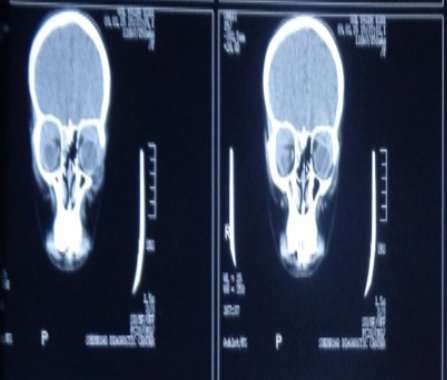

CT scan Orbit (Axial View): Mild Proptosis of the Left Eye

Lab investigations: Hb 11.1 g/dl, RBC 4.27 million/cmm, Hct 32.4 %, MCV 76 fl, MCH 25.9 pg, MCHC 34.2 g/dl, Platelet count 328000/cmm, TLC 11000/cmm, normocytic normochromic picture with DLC showing 80% neutrophils, 15% lymphocytes and 5% monocytes on peripheral smear, ESR 70 mm/1st hour, negative HbS and HCV screening, negative PPD and sputum AFB, normal Liver function tests and normal Renal function tests. Chest X-ray was normal, U/S and CT scan of the abdomen and pelvis were normal. CT scans of the orbits showed bilateral superior orbital masses and mild proptosis of the left eye.